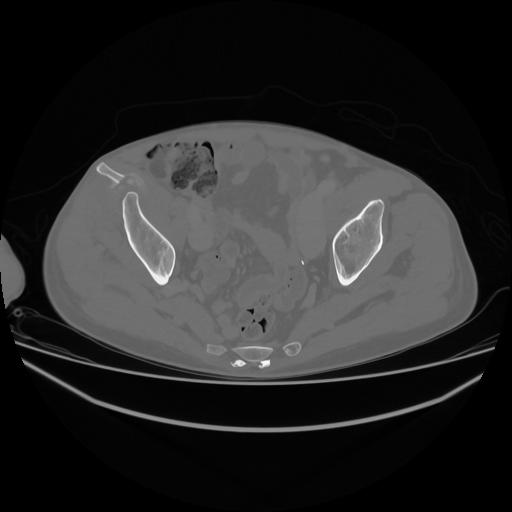

5 CUERPO,CE,Vol,1.0,CUERPO,,